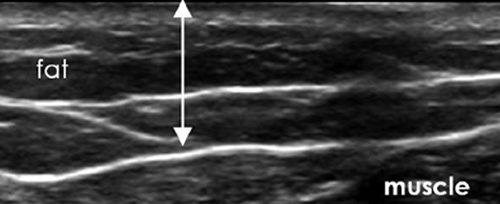

Elite Beauty Toledo performs Tickle Liposuction under ULTRASOUND! Using ultrasound technology increases doctors’ accuracy, can show you the amount of fat you are expected to lose, allows for precise sculpting and extreme skin tightening!

TICKLE LIPO GUIDED BY ULTRASOUND!